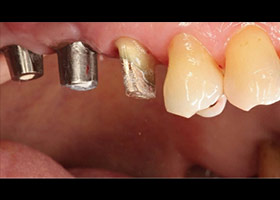

最後裝置假牙

完成照片